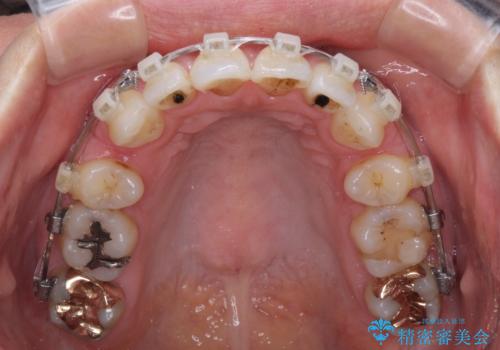

- クリアブラケット

- 2年3ヶ月

通常であれば上下左右の第一小臼歯4本を抜歯して口元の突出感を改善しますが、下顎前歯が1本欠損しており、上下の歯の数がアンバランスであるため、4本抜歯するかどうか悩むところでした。

上顎前歯はやや小さめで、下顎前歯はやや大きめであったため、上下左右4本を抜歯しても左右奥歯の咬み合わせは理想に近い状態を達成できると判断し、上下左右の第一小臼歯4本を抜歯し、ワイヤー装置にて矯正治療を行うこととしました。

当初目論見通り、左右奥歯の咬み合わせはしっかりとさせることができました。

下唇に跡がつくほど飛び出していた上顎前歯も引っ込み、満足のいく仕上がりとなりました。